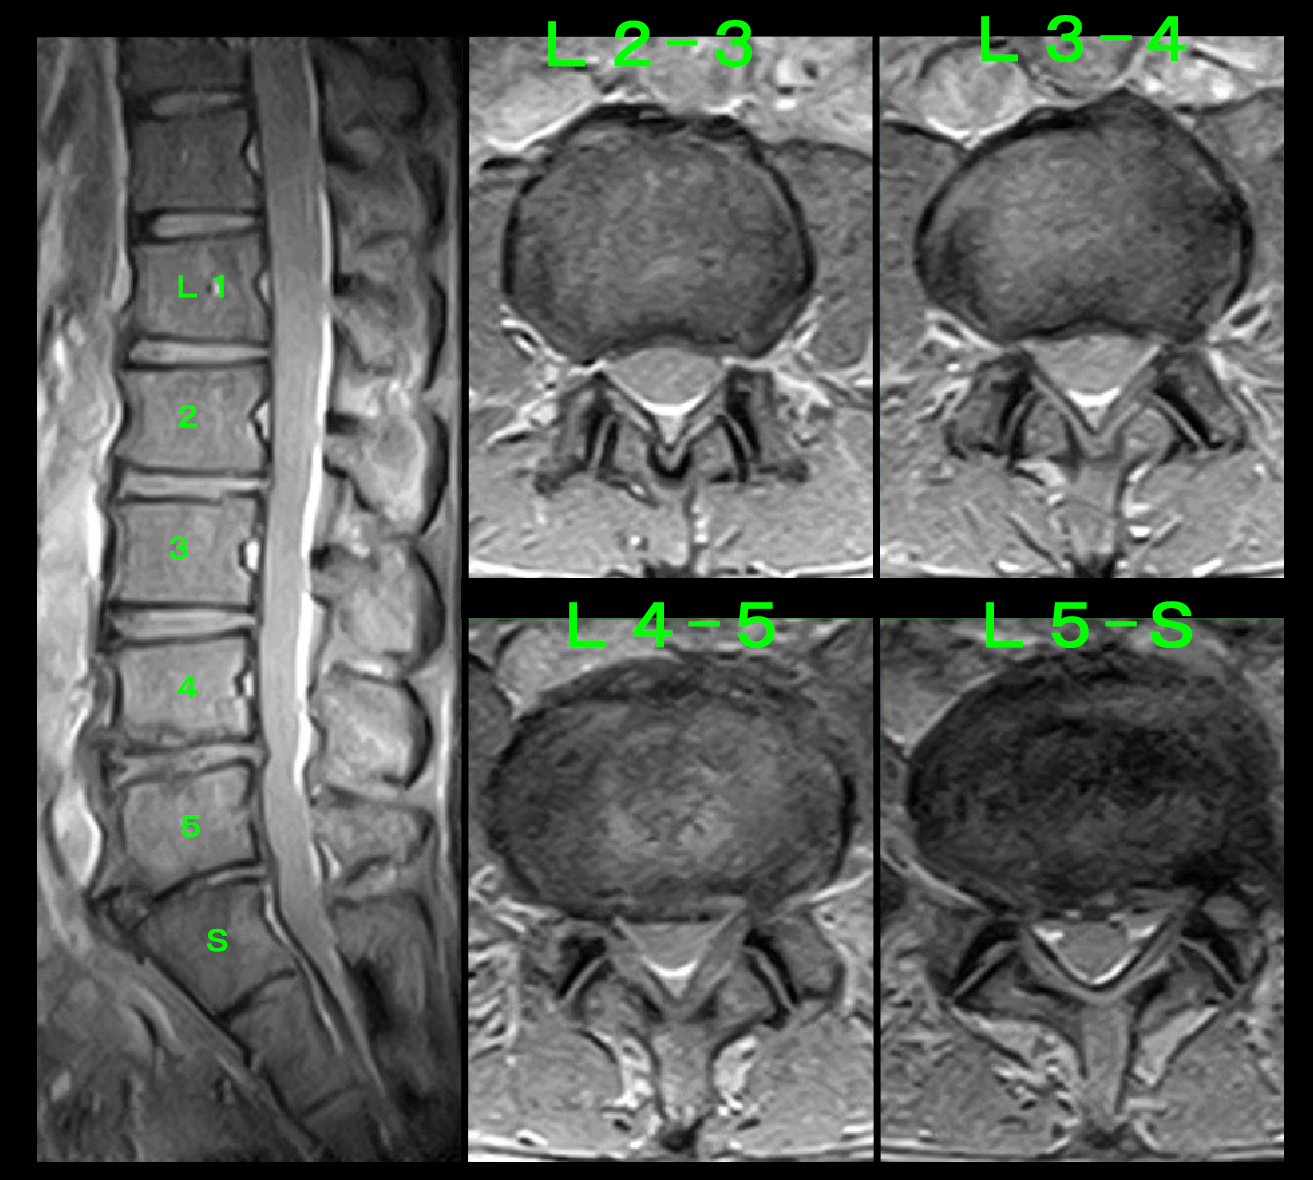

初診時MRI検査を行っています。4年もVAS8の痛みが続いているのですから、必ず痛みの原因となる所見が確認されるはずと考えて検査しています。

71才男 MR1.jpg

通常の椎間板に起因する痛みを検索する画像では、L4-5で椎間板が多少脊髄を刺激していますが、全体として70代としては軽微な加齢所見と評価され、これが4年間VAS8の痛みをもたらしているとは想定できませんでした。